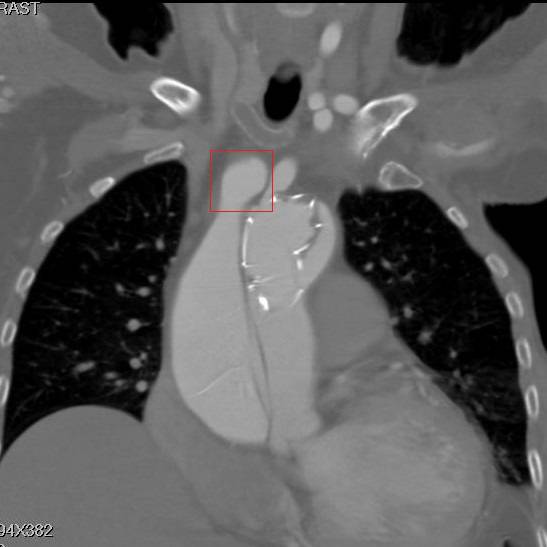

冠状面重建,方框示头臂干看上去完全开口于假腔,左颈总似乎被支架盖住了

细读其原手术记录,术式是杂交手术。于升主动脉内植入一枚覆膜支架,覆膜支架倒装,即植入前将覆膜支架从输送系统中拆出,前后颠倒,并预开窗。支架前端定位在第一内膜破口和冠脉开口之间,该例第一内膜破口和右冠开口有一定距离,作为前端锚定区。先作左锁骨下动脉—左颈总动脉—头臂干人工血管搭桥。支架后端定位在主动脉弓上,为达到良好后端锚定,但避免造成脑部缺血,故在弓上分支开口相对的支架部位剪除且覆膜作预开窗。如果预开窗对位效果不佳,只要左锁骨下动脉没有覆盖,还可通过预先做好的人工血管搭桥为脑部供血。支架从股动脉植入。